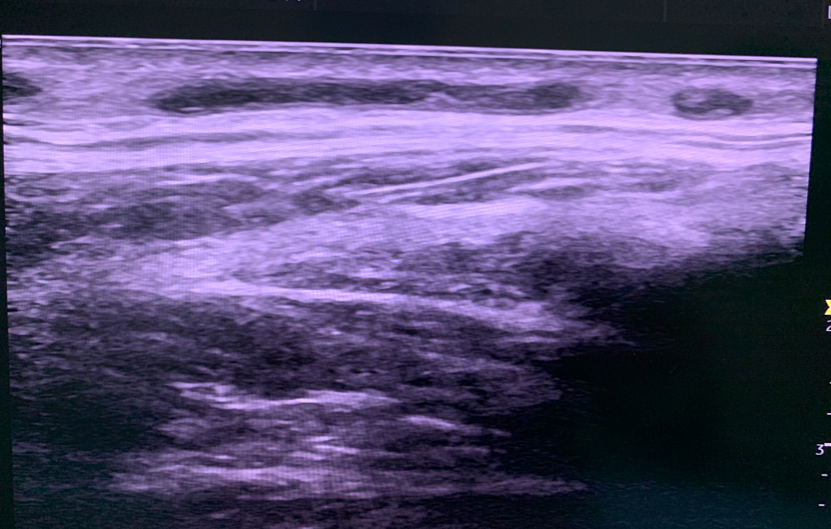

国内首例MOCA手术

2025年8月8日,浙江省人民医院完成了我国第一例MOCA手术。患者为90余岁高龄,心脏功能差,大隐静脉主干表浅,不适合热消融。术中通过4F鞘高速旋转破坏内膜后注入硬化剂,效果理想。